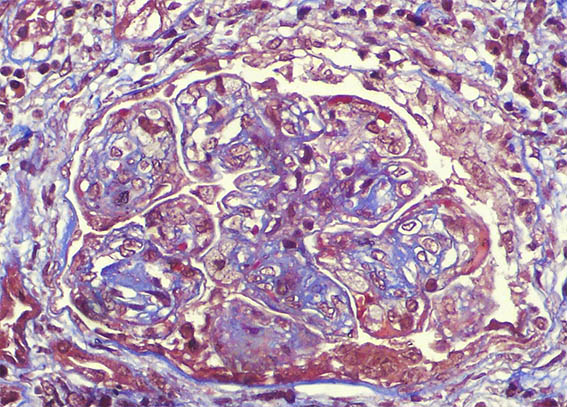

A renal biopsy was done, see the images.

Figure 6. Masson's trichrome stain, X400.